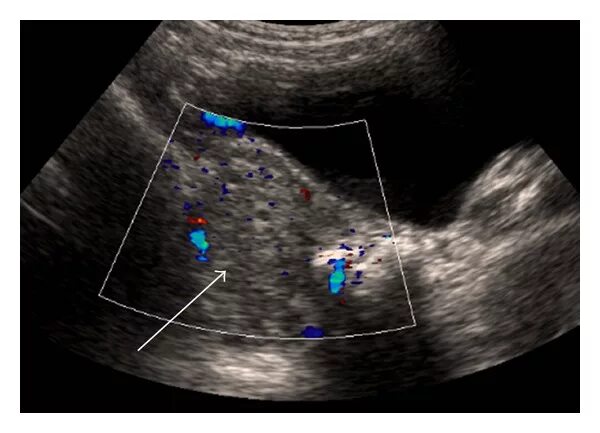

Перекрут придатков матки